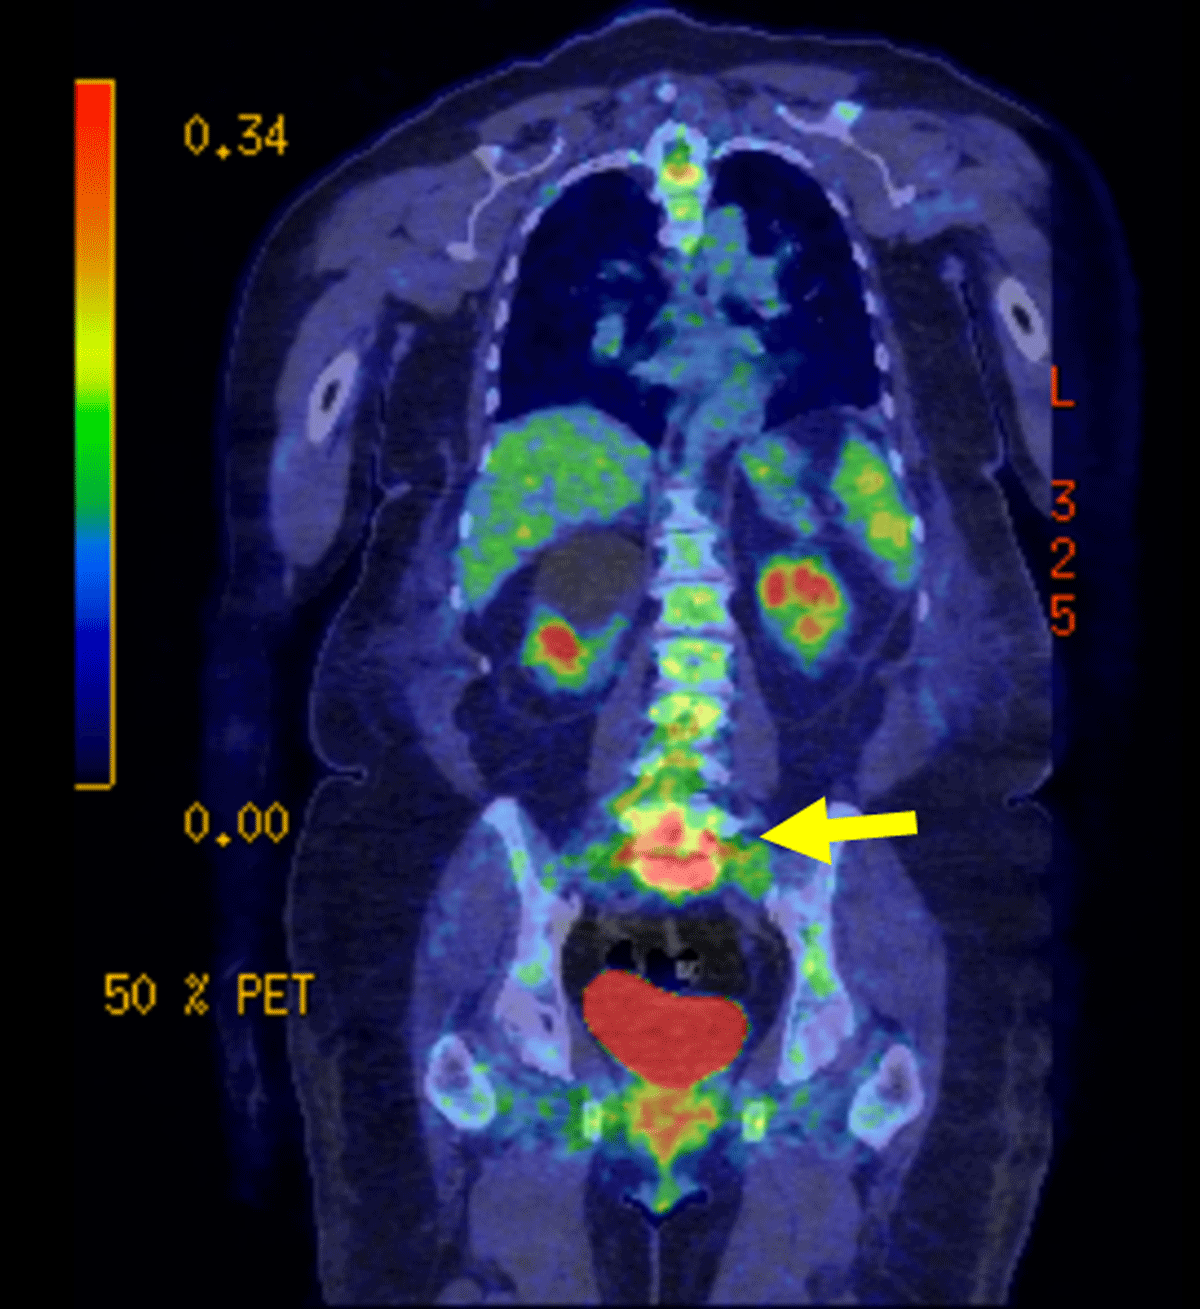

Figure 3

Coronal FDG PET-CT: PET-CT using F-FDG was performed in the context of a possible infection which revealed intense activity at the junction of L5-S1 and the surrounding tissue.

Positron emission tomography CT (PET-CT) using 18F-FDG is highly specific for infectious spondylodiscitis, with some studies reporting up to 100% accuracy in their diagnoses [6].